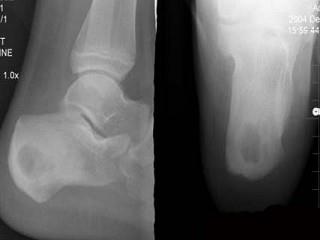

问题 13岁男性患者,右跟骨疼痛不适3周,无发热等其他不适,右跟骨侧、轴位摄片如图示,最可能的诊断是 ( )

选项 A、右跟骨血管瘤 B、以上都不正确 C、右跟骨骨囊肿 D、右跟骨骨巨细胞瘤 E、右跟骨结核

答案 E